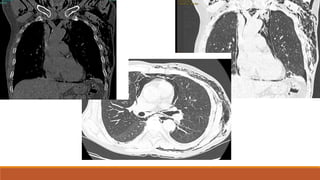

CT of the chest reveals contusion of

the right lung and left lobe.

Also effect is noted on the left side

in the rib with herniation of lung

tissue parenchyma through an

intercostal space.